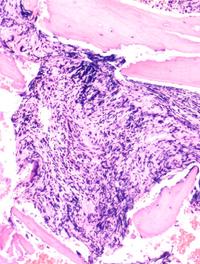

La myélofibrose (MF) est une néoplasie hématologique caractérisée par une anémie, une hématopoïèse extra-médullaire, une splénomégalie, [...]